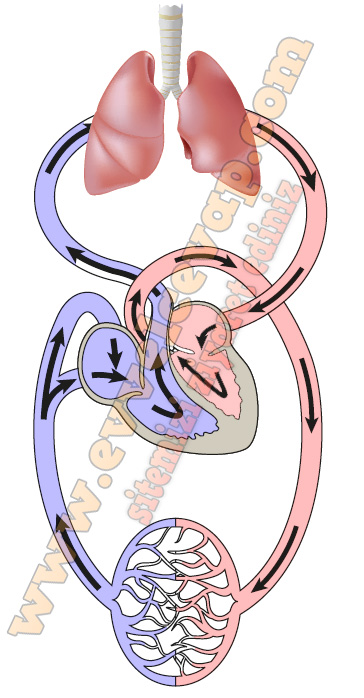

2. Küçük kan dolaşımı ve büyük kan dolaşımının hangi yapı ya da organlar arasında gerçekleştiğini ve hangi amaçla yapıldığını yazınız.

Küçük Kan Dolaşımının Sıralaması;

- Sağ Karıncık

- Akciğer Atar Damarı

- Akciğer

- Akciğer Toplar Damarı

- Sol Kulakçık

- Sol Karıncık

Büyük Kan Dolaşımının Sıralaması;

- Sol Karıncık

- Aort

- Vücut

- Üst ve Alt Ana Toplar Damar

- Sağ Kulakçık

- Sağ Karıncık

3. Yandaki şekilde, dolaşım sistemimizde görevli yapı ve organlar yer almaktadır. Büyük ve küçük kan dolaşımında gerçekleşen olaylara göre şekli uygun biçimde renklendirip kanın hareket yönlerini ok ile gösteriniz.